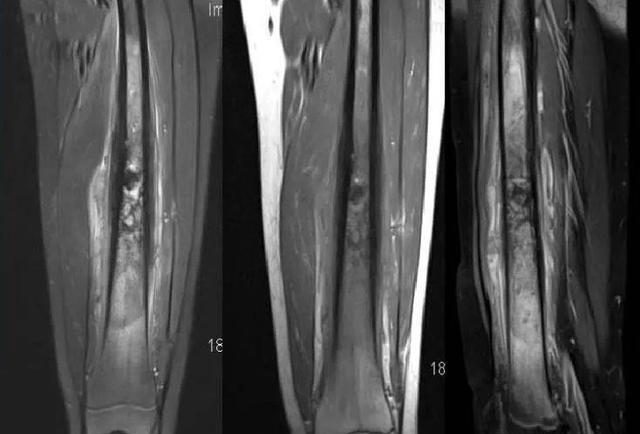

可是好景不长,厄运很快就降临到这个普通的家庭。在12岁那年,李明馨突然出现了皮肤上的异常,小腿布满了青紫的淤斑点。一开始她并没有在意,以为可能是不小心磕碰到了。但随着疼痛的加剧,父母还是决定带她去医院检查。

然而,医生却给出了令人震惊的诊断结果:李明馨患有骨肉瘤癌症,而且已经是晚期了!更糟糕的是,病情已经恶化到了必须马上截肢的地步,否则就会危及生命。即便是截肢,她的存活时间也只有5年左右。